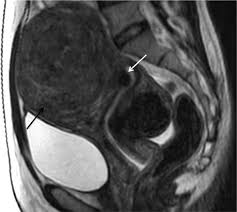

자궁근종은 자궁을 대부분 이루고 있는 평활근(smooth muscle)에 생기는 종양으로, 35세 여성에서 40% 이상이 경험하는 가임기 여성의 대표적인 자궁질환이라고 한다.

가장 흔하게 접하는 오해는 '자궁근종은 유전된다'는 것이지만, 이는 사실과 다르다. 다만 식습관과 환경적인 요인 등으로 인한 가족력은 생길 수 있다고 한다. 또 자궁근종이 있으면 임신이 어렵다고 오해하는 경우도 적지 않다. 하지만 전문의들에 따르면, 자궁근종은 위치에 따라 크게 점막하, 근층내, 장막하 근종으로 나누어진다. 이 중 점막하 근종은 자궁내막을 침범하거나 인접해 있는 경우로 이럴 땐 착상을 방해하거나 유산 가능성을 높일 수 있다고 한다. 다른 위치의 근종도 임신 중 2차 변성이 발생할 수 있고 이로 인한 통증 유발 및 2차적인 조기진통이 발생할 가능성도 있다고 한다.